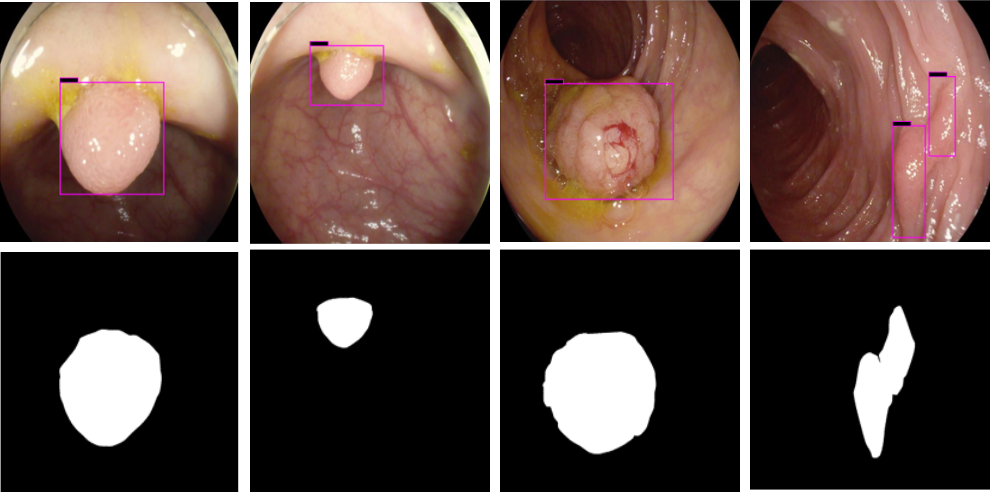

Refer to caption

Figure 6: Example of accurate detection along with the correct ground truth using deep CNN model. The first row shows the detection results for different polyp from data augmentation process. The second shows the ground truth images of test images.

The results shown in Fig. 6 are generated using the proposed deep CNN model on the augmented data set. It can be observed that the proposed model shows better polyp detection performance. As illustrated in Fig. 6, polyps within a frame can be identified at multiple positions, and as noted above in this case, the TP for detection is considered to be 1. The proposed deep CNN model performed better than other benchmark results in terms of the performance metrics listed above, as shown in Table. 2 and Fig. 6.